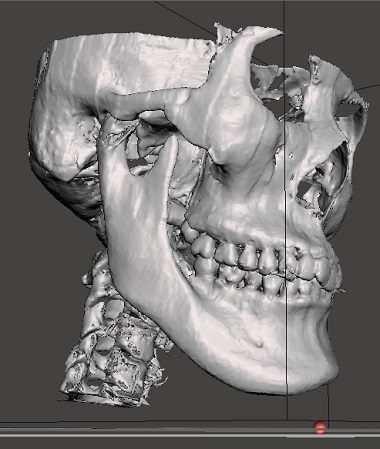

Phần mềm 3D giúp bác sĩ nhìn thấy chính xác các dị tật của bệnh nhân ở các góc độ khác nhau.

Bác sĩ có thể lên kế hoạch phẫu thuật, đo đạc, cắt, thao tác trên mô hình in 3D xương của bệnh nhân với độ chính xác gần như tuyệt đối.